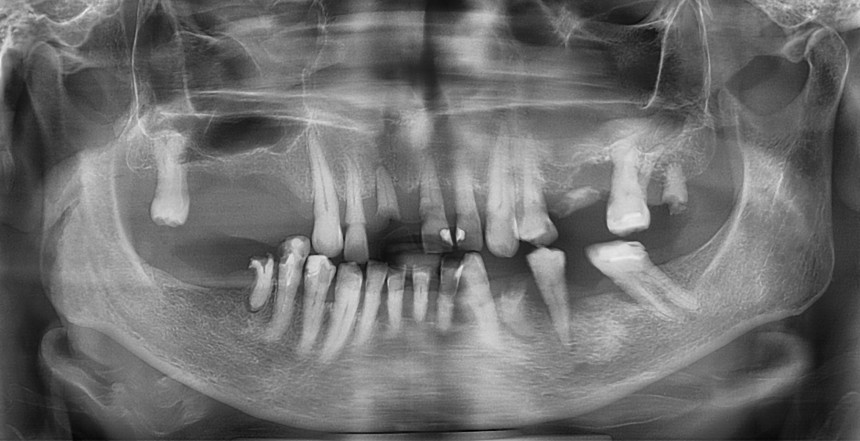

Основными методами обследования перед операцией являются ортопантомография и конусно-лучевая компьютерная томография (рис 12 и 13).

Рисунок 12. Ортопантомограмма. К сожалению, по данному снимку сложно судить о пространственной конфигурации верхнечелюстной пазухи

Ортопантомография подразумевает «перенос» трехмерной структуры в двухмерную проекцию, поэтому в ней неизбежны искажения. Планировать операцию по ортопантомограмме мы можем лишь приблизительно, буквально в пределах понятий «нужен синуслифтинг или нет».

По ортопантомограмме невозможно понять толщину стенок верхнечелюстной полости, их конфигурацию в щечно-небном направлении, нельзя определить, как соотносятся корни зубов с дном верхнечелюстной пазухи. А это, в свою очередь, очень важно при планировании операции синуслифтинга (рис 14).